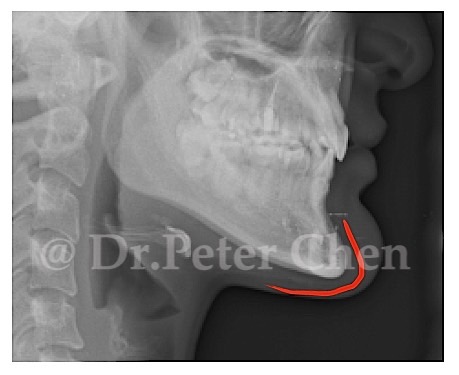

有些下顎骨突出的案例,從 X ray 上 會發現下顎骨前端(Menton)特別會突出一塊,

不笑時因軟組織包住較不明顯,笑的時候因為軟組織變薄了,骨骼的形狀就顯現出來,讓人有下巴多了一塊骨頭的錯覺。

在手術設計上,除了利用正顎手術將下顎骨退後,最好同時將下顎骨前端的骨骼重新雕塑,才能達到理想的效果。